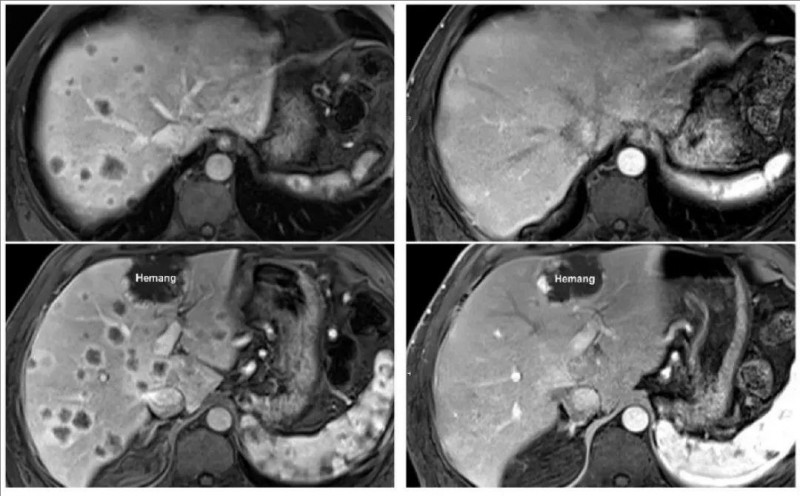

此外,还有一位胰腺癌患者更是创造了奇迹,在 6 周的随访中,数十个肝转移瘤完全消退,这一阶段性成果足以让人看到 TIL 疗法的巨大潜力。